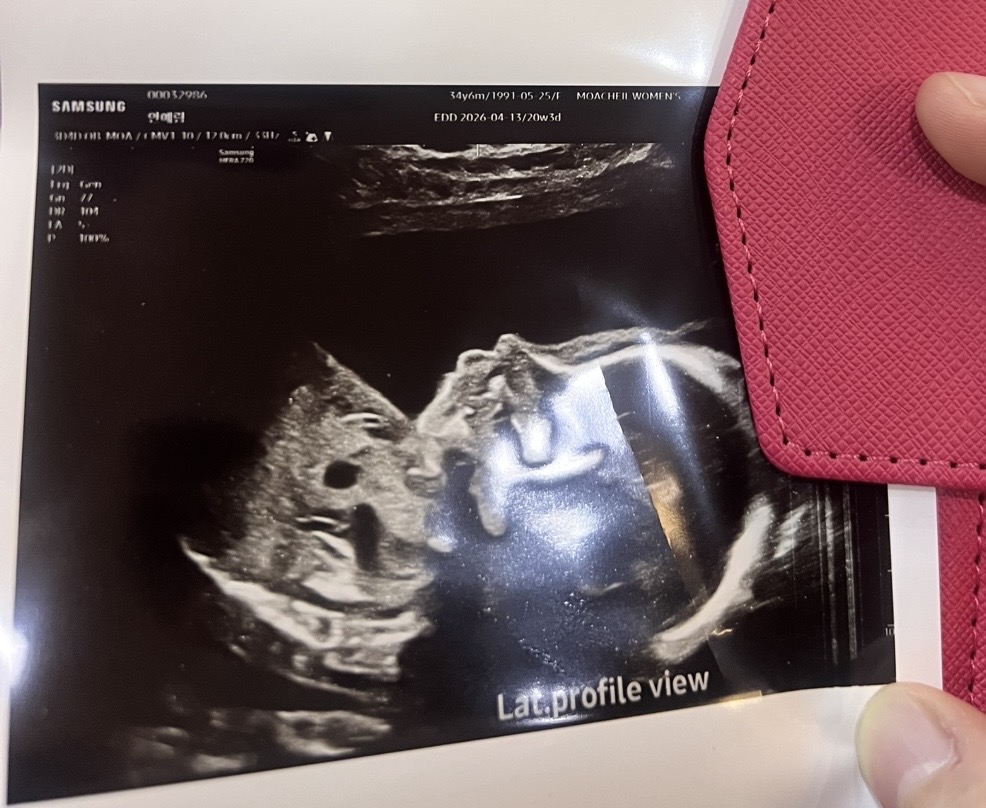

20주차 정밀초음파 찍구 왔어요 ㅎㅎ

아들이라 동글한 제 코보다는 아빠 닮은 코를 원하는데 아직 살이 붙기전이라 모른대요ㅜㅜ그래도 낮은코는 아니겠죠..? ㅎㅎㅎ 둘째인데도 아들 얼굴 너무 궁금해요 ㅎㅎ

헉 20주 초음파는 살이 붙기 전이라 모르는거군요ㅠㅠ..저도 저저번주에 정밀초음파 하구왔는데 초음파 쌤이랑 담당원장님이 옆모습 너무 예쁘다구 코 엄청 오똑하다고 칭찬하셨는데ㅠㅠ살붙기 전인거라니이이....... 그래도 리베리맘님 아가 코뼈 각도가 높아보여서 낮지 않을거 같아요!!!! 제 딸랑구도 높기를 바라며...🙏